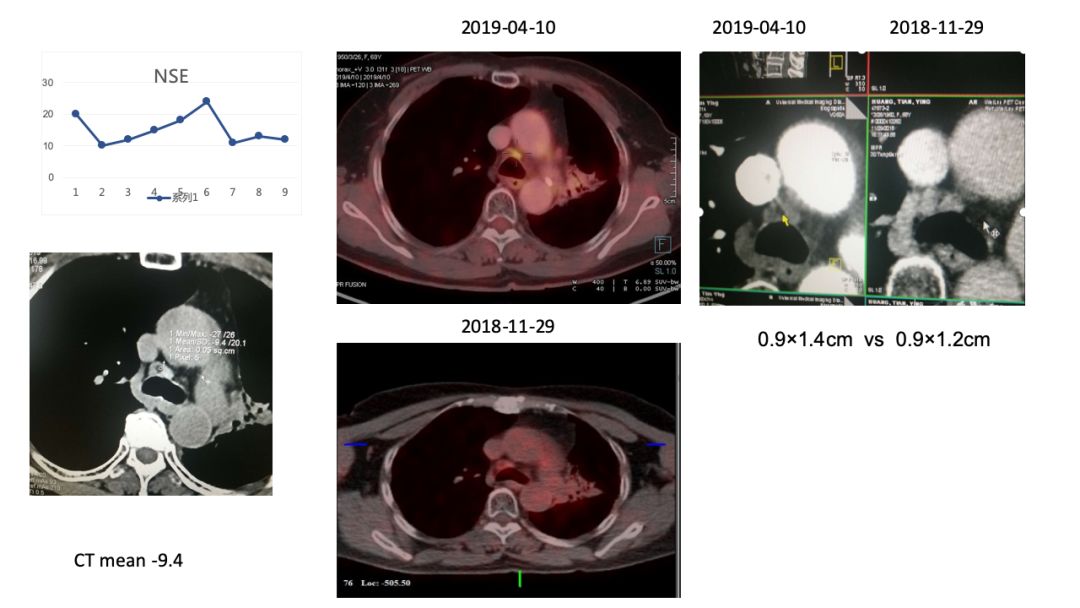

5)4R,10R组LN(非放疗区)1年来随访大小未见变化,4R实性程度增高,代谢增高2倍。

② EBUS或者纵隔镜检查4R,若阳性,下一步如何治疗?

初诊时4R,10R LN增大,PET考虑炎症,未行放疗,随访期间淋巴结大小无变化,NSE稳定正常,建议观察,3个月后复查CT。